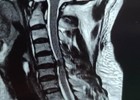

近期,年轻的阿明突然出现一侧肢体无力,开始家人以为“脑中风”,后明确原来为颈椎病椎间盘急性脱出,在广东省人民医院(下称“省人医”)帮扶下,我院骨科予以手术治疗,2023-10-24